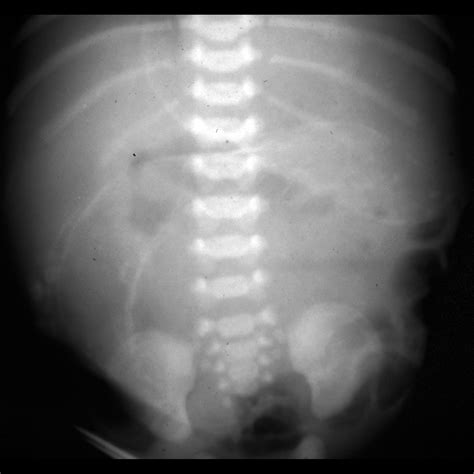

A distended belly in a newborn refers to an abnormally swollen or enlarged abdomen. This condition can be caused by various factors, ranging from normal digestive processes to more serious medical issues. It is essential for parents to recognize the signs and seek medical advice when necessary.

• Imaging Tests: In some cases, imaging tests such as X-rays or ultrasounds may be ordered to visualize the intestines and identify any blockages or abnormalities.